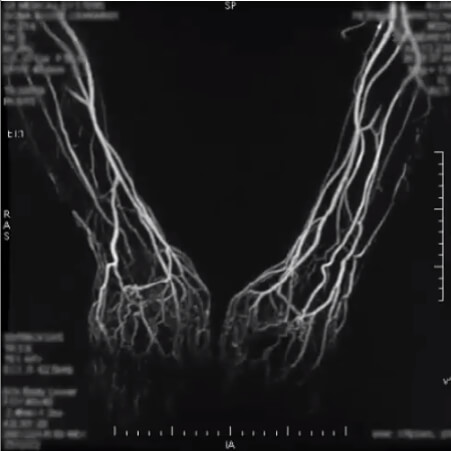

This second image is a 4D sequence of an upper extremity MRA. A 4D-sequence, which is a 3D-sequence with a fast time resolution. The volume is refreshed very quickly.